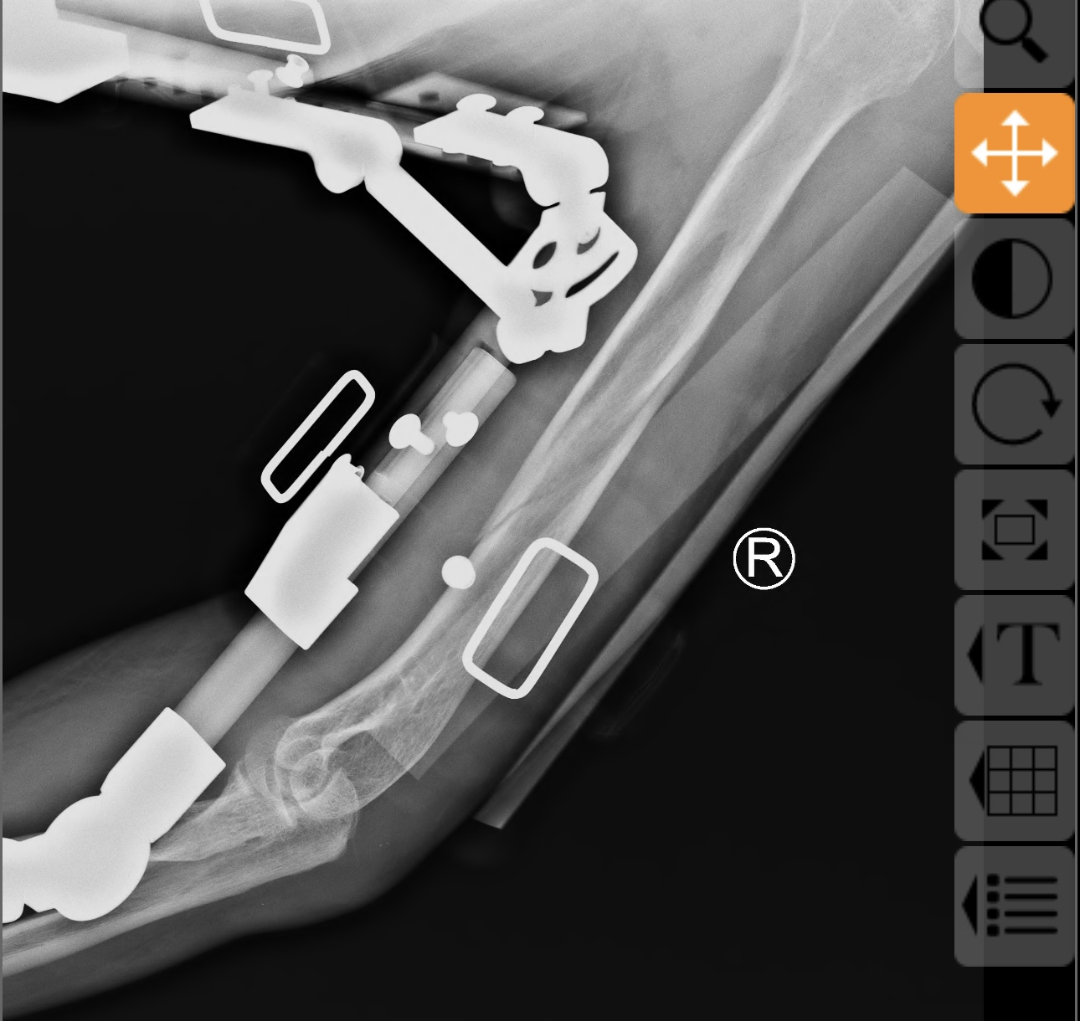

在董博主任医师和周健副主任医师的精准操作下,通过专业的手法复位技术,成功将移位的骨折端恢复至正常解剖位置,随后为患者佩戴外固定支架进行稳定固定。复位后的X线片显示,骨折对位对线良好,患肢末梢血运正常,治疗效果显著。